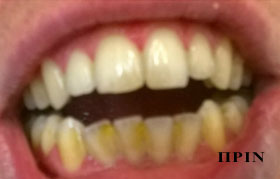

λεύκανση

σοδοβολή